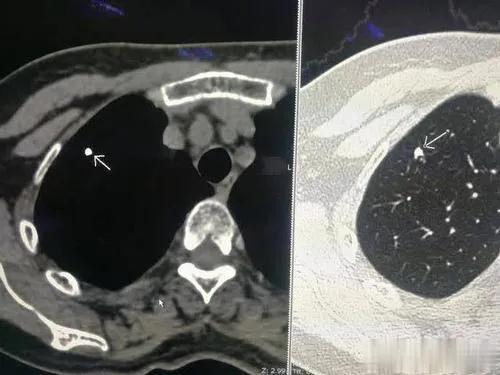

肺部結(jié)節(jié)是指在胸部影像學(xué)檢查中發(fā)現(xiàn)的直徑小于3厘米的球形病灶。肺部小結(jié)節(jié)是指直徑小于1厘米的球形病灶。

1、肺部陳舊性感染病灶

這是引起肺部結(jié)節(jié)最常見的原因之一。一個人曾經(jīng)患過肺炎,等到肺炎愈合之后(很多時候,患者自己可能都沒有感覺),在這個地方就會形成一個結(jié)節(jié),就相當(dāng)于我們的皮膚劃破愈合之后,會留下一個傷疤一樣。這種病灶通常還會有鈣化,就會顯得特別亮。這種情況下,人一般沒有任何癥狀,也沒有任何不舒服。

圖片2.jpg